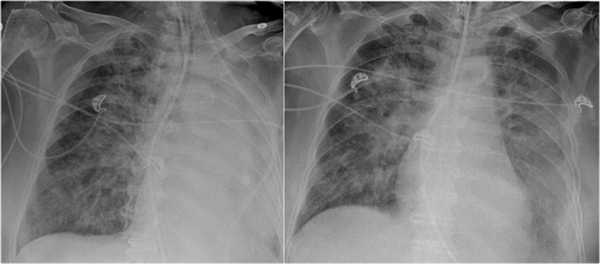

На рентгенограмме органов грудной клетки определяется тотальный ателектаз правого легкого со смещением средостения вправо. На втором снимке представлен тот же пациент, но после лечения. Легкое воздушное и положение средостения в норме. Распространенной причиной тотального ателектаза является неправильно установленная вентиляционная трубка, которая расположена слишком низко и тем самым обтурирует главный бронх.

На ниже представленном снимке представлен пациент с тяжелой бронхопневмонией и тотальным ателектазом. Причиной ателектаза явилось обтурация бронха слизью. После отсасывания мокроты аэрация левого легкого была восстановлена.